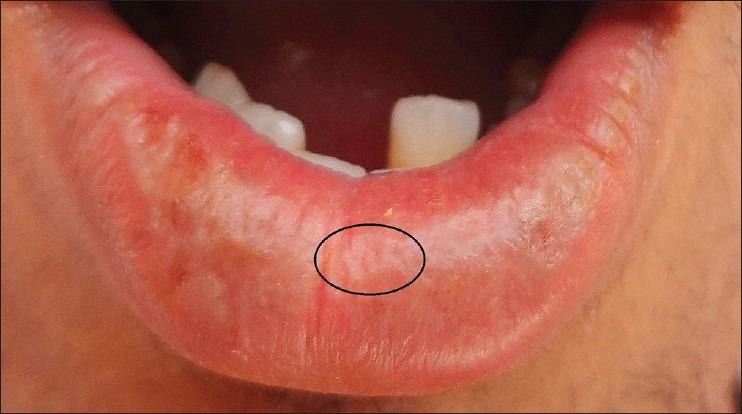

利用唇纹鉴定法进行性别鉴定。

Gender determination using cheiloscopy.

The present study was designed for documenting common patterns, as well as their variation in the study population, with objective of evaluating uniqueness of the lip print pattern among the study population, as well as to evaluate the possibility of gender determination.

In our study, none of the lip prints were identical, thus confirming the role of lip prints in individual identification. Dots, reticular and complex patterns were significant in gender determination.

结论

在我们的研究中,没有两份唇纹是相同的,从而证实了唇纹在个体识别中的作用。点状、网状和复杂模式在性别判定中具有重要意义。